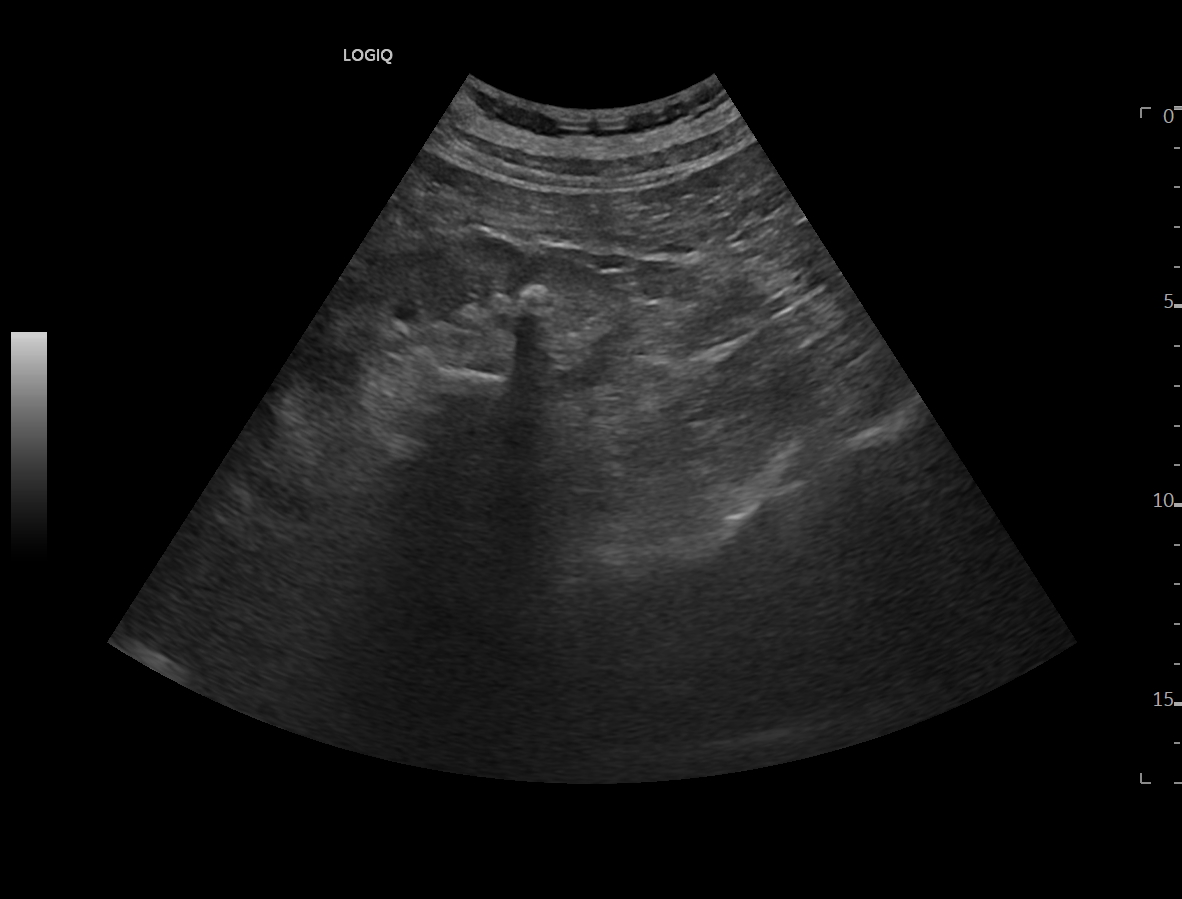

Ya en urgencias hospitalarias, se realiza ecografía clínica donde se aprecia ureterohidronefrosis derecha grado IV con pérdida completa de ecoestructura renal por el incremento del volumen que presenta, no presentando las mismas alteraciones en el lado izquierdo, pudiendo esto indicar una obstrucción completa no resuelta.

La ecografía clínica reglada informa de dilatación de pelvis renal de hasta 5,7 cm con aumento de tamaño renal hasta 13 cm, apreciando litiasis obstructiva de 12 mm en uréter distal a unos 5 cm del meato ureteral derecho.